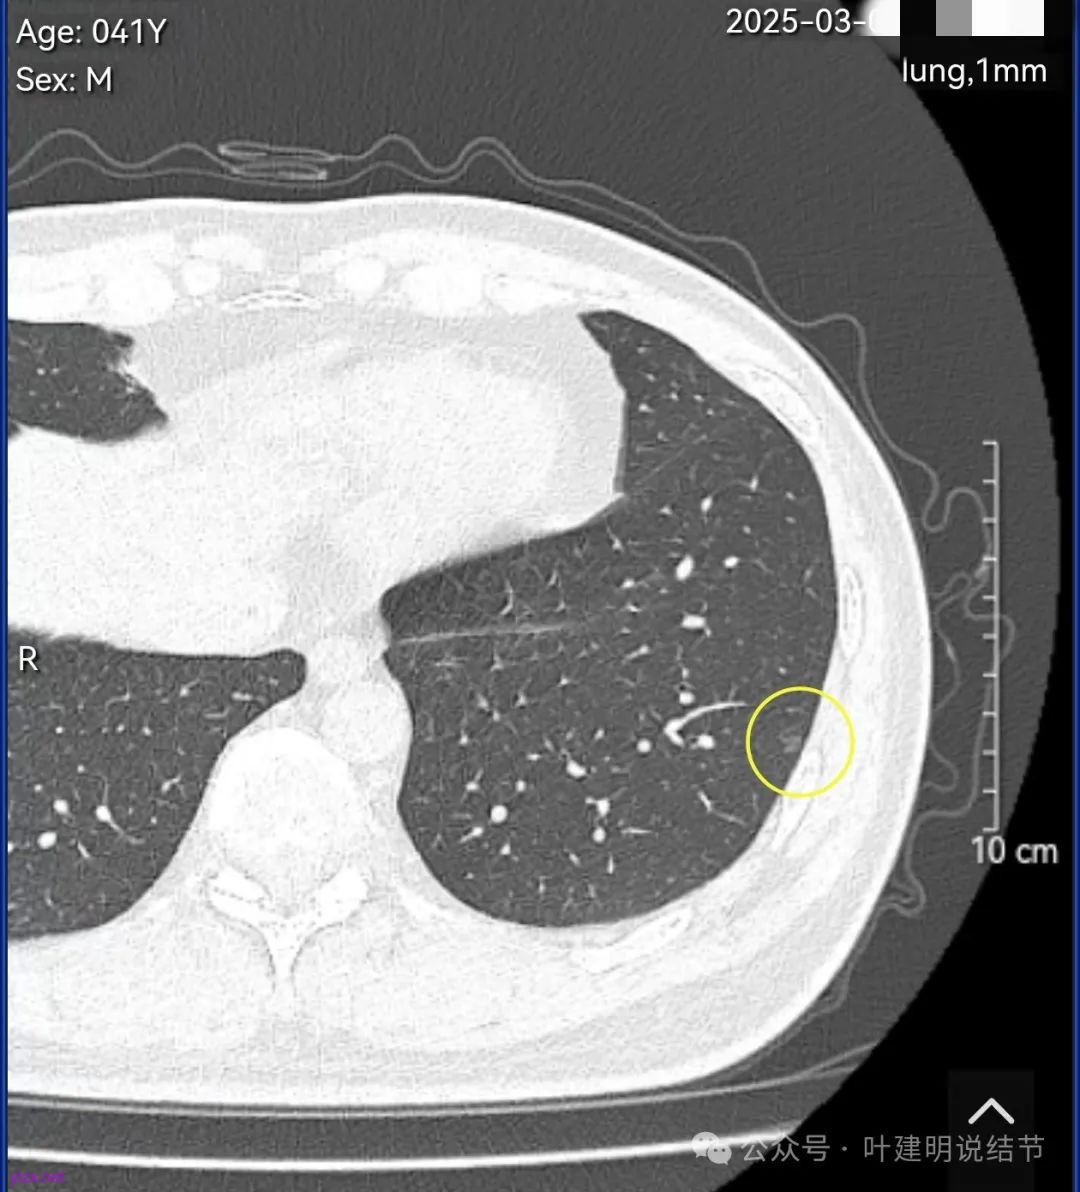

结友男性,41岁,具体病史记不得了,下面是请他重新发我的术前CT报告中截图的影像。

左下叶胸膜下很淡但边缘不光滑的磨玻璃结节,考虑肺泡上皮增生可能性大,或者肺泡间隔增宽。